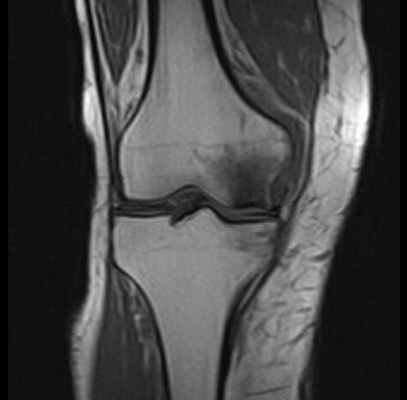

Болезнь Альбека: асептический некроз костей

МРТ при некрозе костей колена. Нормальная ширина суставной щели, суставный хрящ ещё не поврежден. Отчетливое изображение некроза внутреннего мыщелка бедренной кости. © Prof. Dr. med. Sven Ostermeier

При недостаточном кровоснабжении костей погибают отдельные костные клетки. Таким образом некроз кости (Болезнь Альбека) означает потерю костного вещества в коленном суставе. Другими словами, остеонекроз — это отмирание костных структур.

Диагностика заболевнаий коленного сустава.© Gelenk-Klinik / Prof. Dr. Sven Ostermeier

Рентген проводится в любом случае. Однако видимые изменения в суставе можно установить лишь на прогрессирующей стадии болезни. Одним из главных сигналов Болезни Альбека на рентгенограмме является склерозирование - болезненное уплотнение костной ткани, которое возникает посредством перенагрузки коленного сустава.

На ранней стадии Болезнь Альбека можно диагностировать при помощи магнитно-резонансной томографии МРТ, которая показывает характерную, болезненную отечность. Измерение плотности костей необходимо для исключения остеопороза всей костной системы человека.